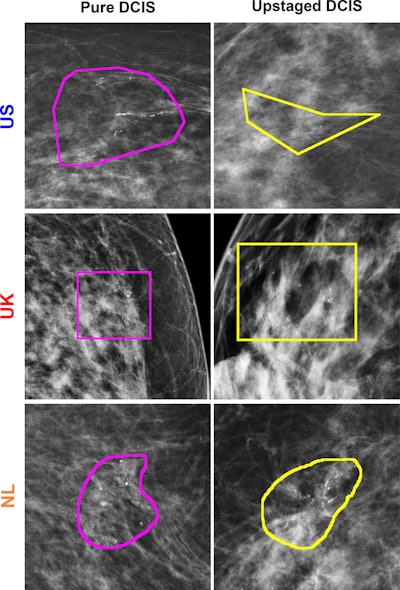

Examples of correctly predicted lesions among three countries using the model trained on images from the U.S. dataset. Lesion annotations were provided by the study radiologists at each site. The regions of interest indicate lesion annotations.RSNA

Hou and colleagues evaluated the performance of radiomics models tested in three national datasets from the U.S., the U.K., and the Netherlands. The study included data collected between 2000 and 2021, and all women were diagnosed with DCIS at core-needle biopsy.